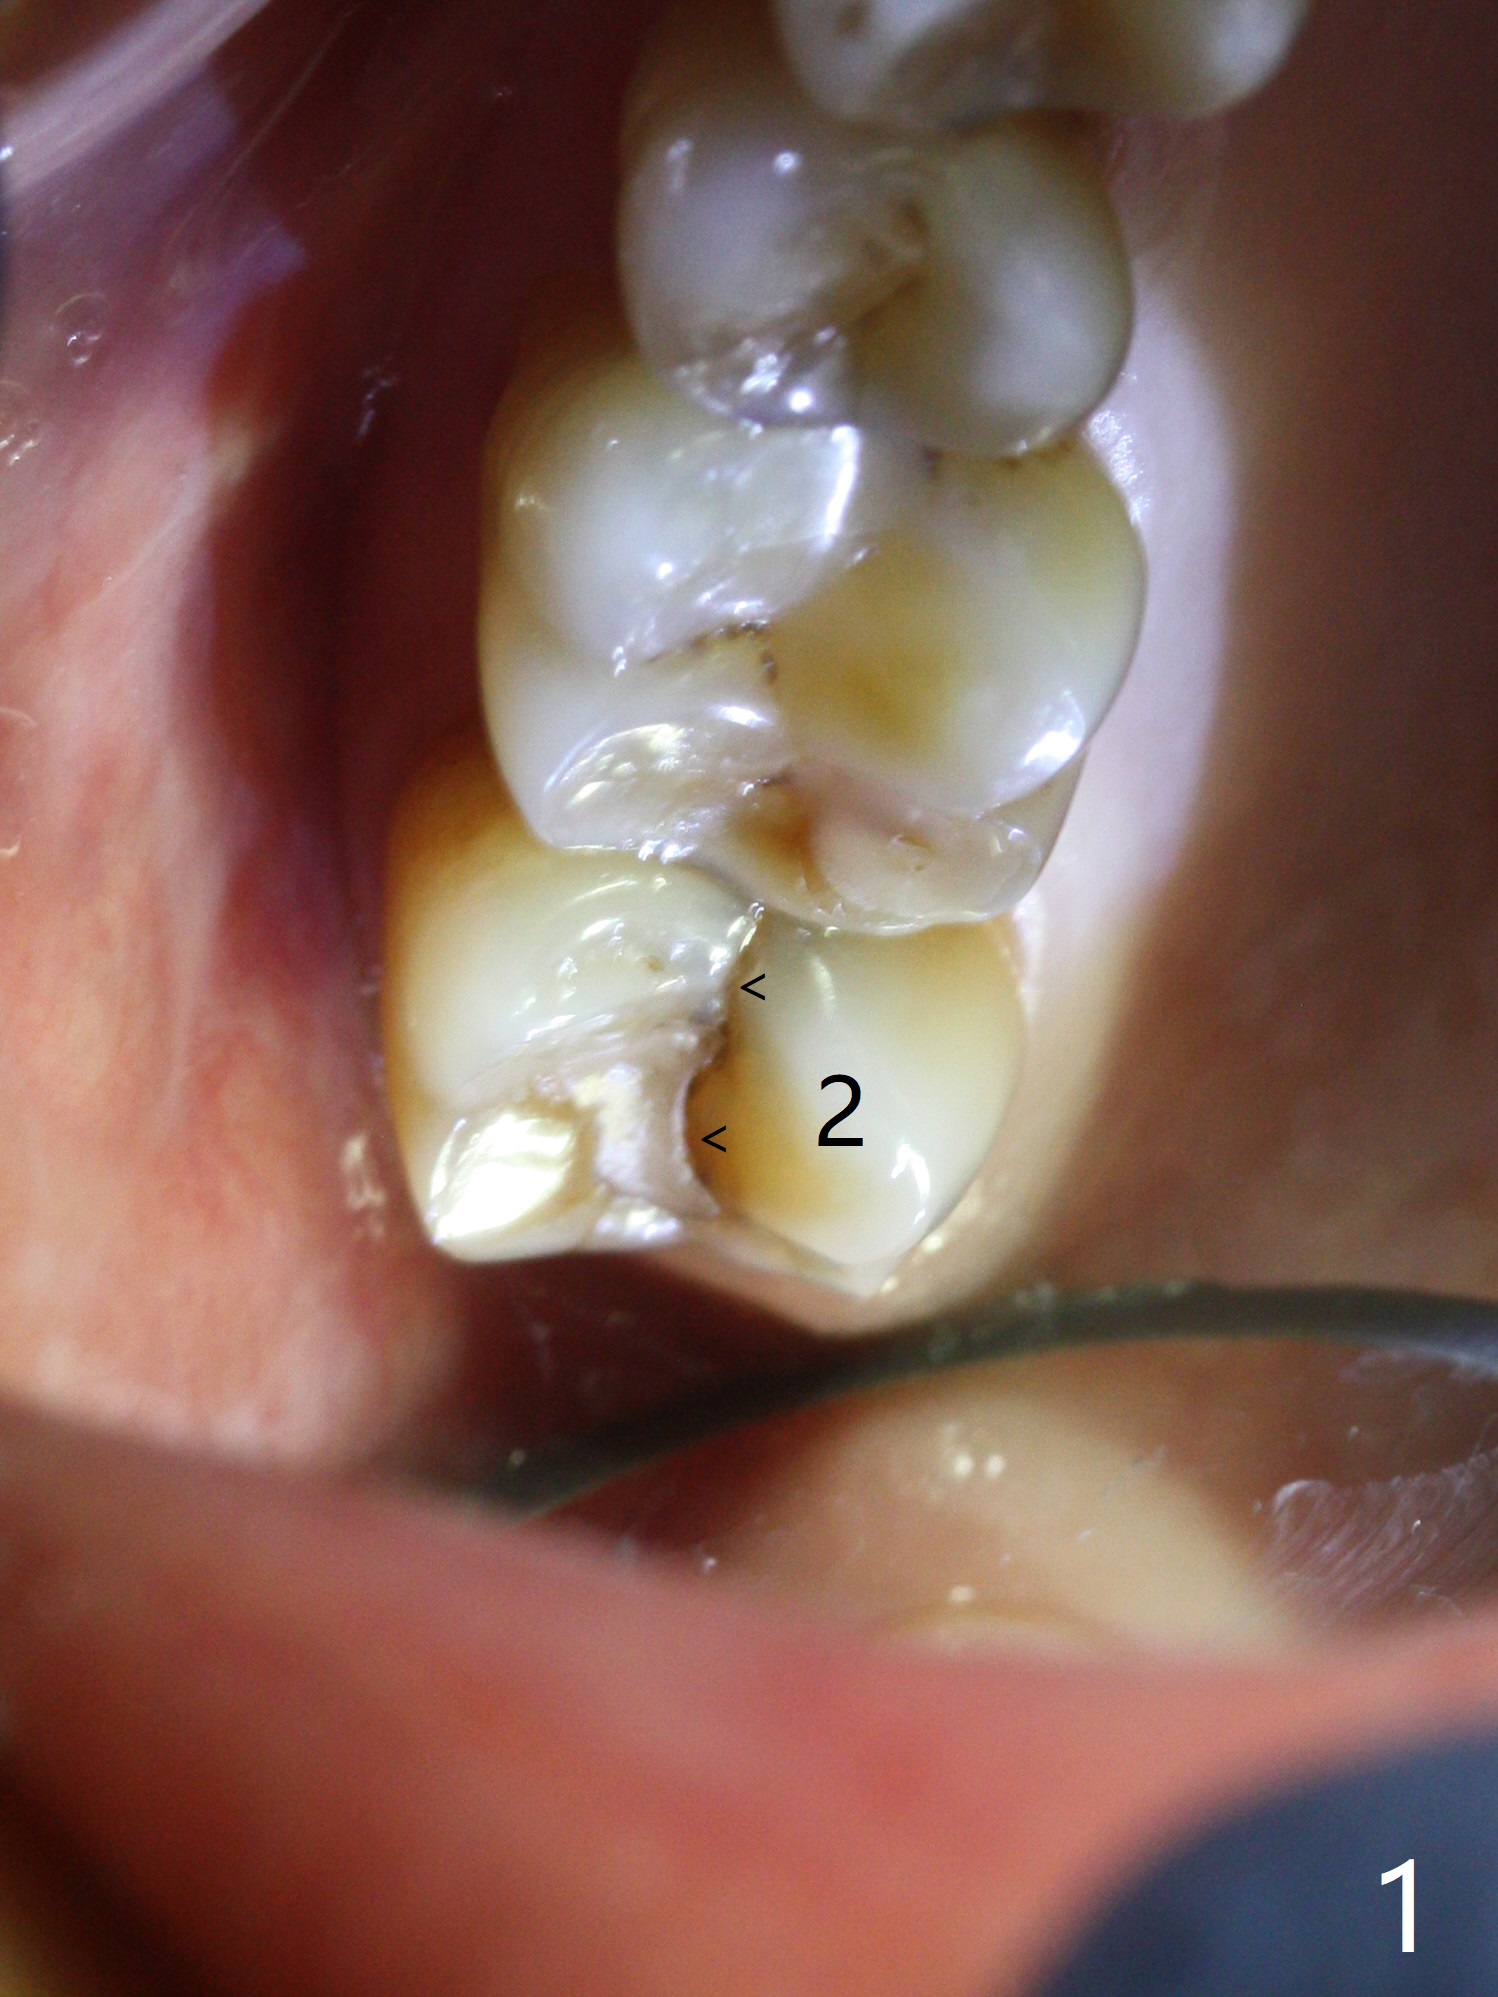

While the tooth #2 has a mesiodistal crack line with symptom (Fig.1 arrowheads, crown pending), the tooth #15 has a mesiodistal fracture (Fig.2). Immediately preop 5x5 cm CBCT (Fig.3) confirms the palatal (P) fracture with palatal bone loss. Although a 5x7.3 mm implant fits the site by design (Fig.4), a much longer implant is required to achieve primary stability past the sinus floor using IBS Magic Expanders (Fig.5,6 (20-30 Ncm; sinus lift with PRF membrane and allograft)). In contrast, primary stability could not be obtained by engaging dummy implant to the socket walls. A short implant without sinus lift is associated with less obvious complication such as fibrointegration. The implant seems osteointegrated 4.5 months postop (Fig.7). The abutment is changed to 6.5x4(5) mm before impression. There is no bone loss 5 months post cementation (Fig.8 (11 months postop)). It is the same 2.5 years post cementation (Fig.9,10).